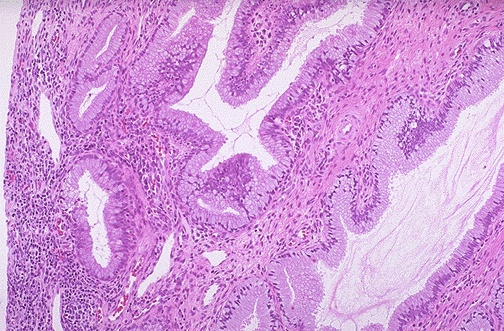

Image 3.3

Microscopically, the cervix is seen here at medium power. (Remember, the endocervical glands are not true glands, but only invaginations of the surface endocervical mucinous epithelium into the fibromuscular stroma.)